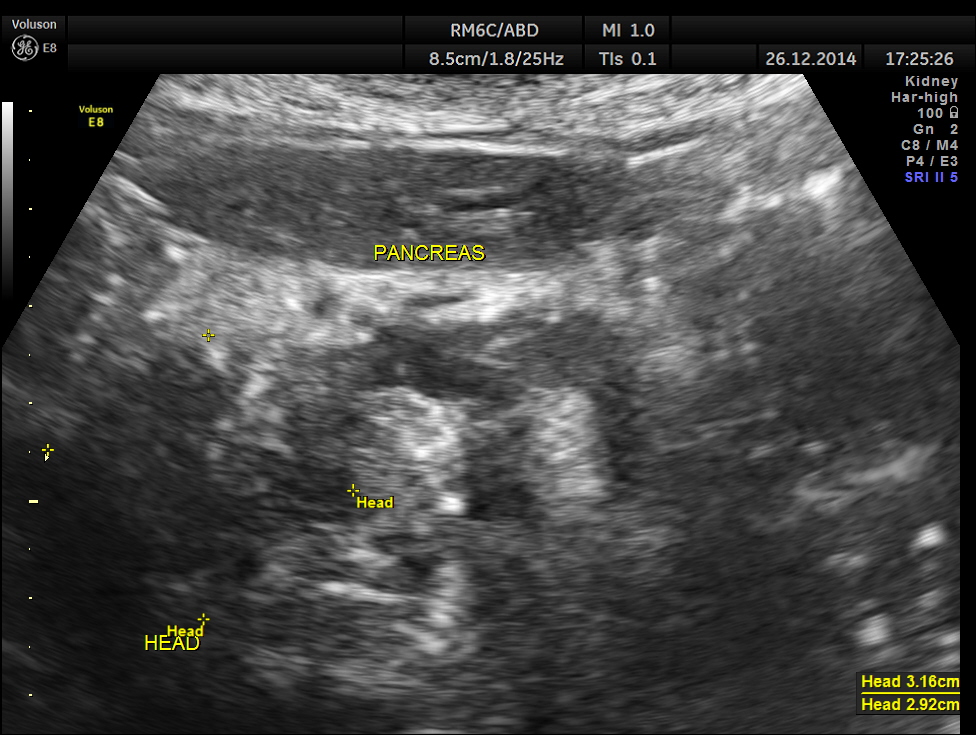

This was a 82 year old lady being evaluated for abdominal pain . Her serum bilirubin was very high and she was referred for an ultrasound .

the head region of the pancreas shows an irregular mass lesion

This was a case of Carcinoma of the head of the pancreas , causing biliary obstruction and also pancreatic ductal obstruction , with possible peritoneal deposits.